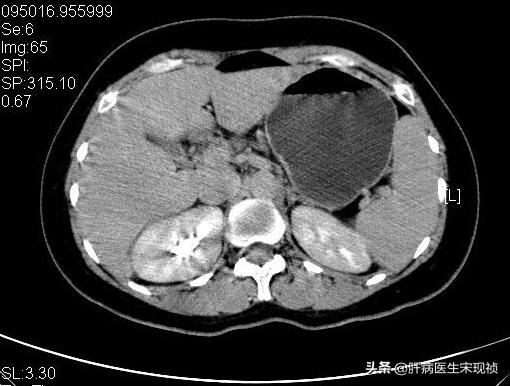

通过影像学检查,如ct、超声、核磁共振等项目确诊是良性还是恶性。

3、肝硬化:患者如果做超声检查或CT检查会发现肝脏内有许多硬化结节,但这些结节的直径多数不超过2cm。核磁共振对鉴别硬化结节和肝癌结节最有帮助。